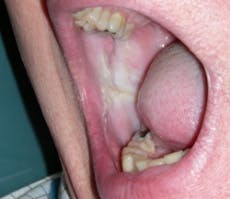

Morsus in Latin means bite. Morsicatio buccarum is biting or chewing of the buccal mucosa; morsicatio labiorum is chewing the lip area (see Figure 2) and morsicatio linguarum is chewing on the borders of the tongue (see Figure 3). The habit may be chewing, biting, or chronic pressure of the tissues. Thicker areas of keratosis may be observed as noted in Figure 3 when the patient continually causes an assault on the oral tissues.

Etiology: Chronic trauma to the tissue causes a defense mechanism to occur in the body. The tissue responds to friction by producing keratin and becoming thickened in what is termed hyperkeratosis. Depending upon the degree of trauma, the tissue may also become ulcerative and eroded in areas. Tissue in the wet areas of the body become whiter in color, just as the skin does when kept in water too long.